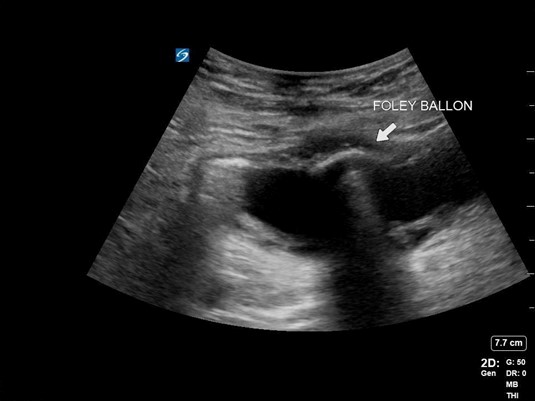

A 59-year-old male with a longstanding history of BPH and urinary retention presented with a chief complaint of suprapubic abdominal pain and non-draining of his foley catheter. He stated that his catheter was changed every 8 weeks and had just been changed the prior month. On examination, his catheter was found to be obstructed with urinary sediment and clot and was removed with a plan for exchange. When the new catheter was placed and the balloon inflated, the patient reported significant pain. A POCUS image of the bladder revealed the following:

Figure 4. Image of foley balloon inside bladder

Discussion

Foley catheter insertion can be challenging in the patient with BPH. POCUS can be especially useful in identifying the location of the catheter, with the balloon creating a hypoechoic shadow artifact. When the patient’s urinalysis resulted, he was found to have a catheter-associated UTI (CAUTI) causing his pain, but the catheter was appropriately placed.